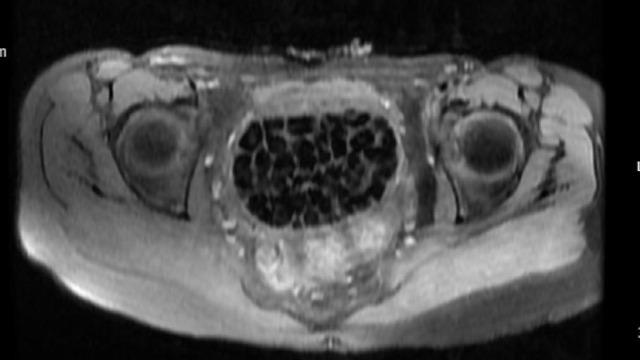

Genç kızın ameliyat işlemleri başlatılırken 11 Eylül’deki operasyon sırasında doktorlar da şaşkınlık yaşadı. Öztürk’ün vücudundan 287 adet çeşitli ölçülerde taş çıkarılırken üroloji ve jinekolojik onkoloji ekibi operasyonu başarıyla tamamladı. Taşların sayısını duyan genç kız ve ailesi şok olurken operasyonun ardından karın ağrıları dinen Öztürk, rahat bir nefes aldı. Tedavisi sonrası taburcu edilen genç kız yaşadıklarını anlatırken, operasyonu gerçekleştiren Üroloji Uzmanı Doç. Dr. Erkan Erkan ile Jinekolojik Onkoloji Uzmanı Op. Dr. Emin Erhan Dönmez de nadir olduğunu ifade ettikleri vakaları hakkında bilgi verdi, önemli uyarılarda bulundu. Öte yandan, genç kızın vücudundaki 287 taşın tetkiklerdeki görüntüsü dikkat çekerken taşlar üzerine de incelemeler yapılacak.

Hastasının durumuna yönelik konuşan Üroloji Uzmanı Doç. Dr. Erkan Erkan, "Hastamızın 2004 yılında doğduğunu ardından doğar doğmaz ekstrofi vezika dediğimiz 50 binde bir görülen bir anomaliden dolayı art arda ameliyatlar geçirdiğini öğrendik. 10 yaşında yine bir ameliyat geçirmişti, gerekli görüntüleme ve tetkiklerimizi yaptırdık. Normalde mesanesinin olması gereken yerin hemen arka kısmında taşlarla dolu bir kese olduğunu gördük, bunun üzerine ek görüntülemeler; MR çektirdik. Hastamız çelişkili açıklamalar almıştı, kendi radyolojik kliniğimiz ve edindiğimiz konsültasyonlarda taşların mesanede değil vajinal boşlukta oluştuğunu düşündük, bir planlama yaptık. Kadın doğum hocamızın da çabasıyla taşları tamamen temizledik ardından ileride normal bir hayat sürmesi bakımından oraya plastik cerrahi yaptık. 287 adet taş çıkardık, pratikte gerçekten görünce çok şaşırdık çünkü bu aynı zamanda literatürde çok nadir görülen bir olay. Biz ameliyata hazırlanırken de teorik olarak biraz araştırdık. Literatürde gördüğümüz kadarıyla buna benzer bu tanıma uyan bir vaka vardı. Literatürde sanırım yayınlanmış 2’nci vaka olacak. Farkındalık çok önemli, bilinçli bir hastamız vardı. Doğumsal anomaliyle doğan çocuklarımızda ileride bunlara bağlı bazı sıkıntılar çıkabileceğinin öngörülmesi lazım. İlgili tedavilerini alsalar bile düzenli takiplere gelmeleri gerekiyor. İleride eğer dikkat etmezse ki zannetmiyorum, tekrarlayabilir. Bu rahatsızlık ekstrofi vezikal epispadias durumu çok nadir bir durum" dedi.

Genç kızın uzun süredir devam eden karın ağrısı olduğunu söyleyerek sözlerine başlayan Jinekolojik Onkoloji Uzmanı Op. Dr. Emin Erhan Dönmez, "Mesane taşları olduğu düşünülerek daha büyük bir hastaneye refere edilmiş. Aramızda mini bir konsey yaparak muayene ettik. Vajen bir hazne görevi görerek orada durağan bir idrar, uzun süre beklediği için idrar içindeki minerallerde çökerek taşlar oluşmuş. Mesanedeki idrarın vajene akmış olabileceği ve vajende göllenen idrar nedeniyle taşların burada oluşacağını düşündük, ameliyatımızı planladık. Ameliyata tanı amaçlı girmiştik, sistoskopi (Mesane gibi idrar yollarını kapsayan kısımlardaki rahatsızlıkların teşhis ve tedavisinde kullanılan endoskopik bir yöntem) dediğimiz ameliyatı Erkan Hocam ile birlikte gerçekleştirdik. Önce mesaneyi bir görüntüledik, mesane tabanına yaklaşık 2-3 cm’lik bir alandan vajene fistülize olduğunu gördük. Mesaneden vajene geçtiğimiz esnada tüm vajenin taşlarla dolu olduğunu gördük. Tanı amacıyla girdiğimiz ameliyatta her şey de olağan gittiği için tedaviye geçtik. Taşların çıkabileceği kadar bir genişlik sağladık. Daha sonra yaklaşık en büyüğü 2,5 cm boyutlarında olan, irili ufaklı 287 tane taşı ameliyat esnasında çıkarmış olduk. Taşların tekrarlamaması için idrarın göllenmemesi, en azından dışarıya rahatça boşalabilmesi için vajinal rekonstrüksiyonu sağladık. Ameliyatta da herhangi bir problem yaşamadık. Literatürü Erkan Hocam ile birlikte değerlendirmiştik. Primer olarak vajende birikmiş olan bu kadar çok sayıda taşla ilgili bir makale görmedik, rastlamadık" dedi.